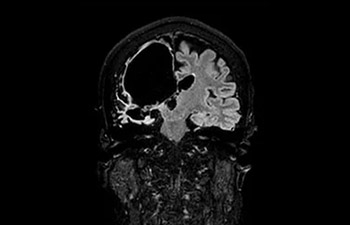

En una sociedad en la que los reembolsos son cada vez menos cuantiosos y las enfermedades crónicas se traducen en un aumento de los procedimientos de RM y en tiempos de espera más largos, los servicios de radiología se ven sometidos a una presión cada vez mayor. La aceleración pone en riesgo la calidad de la imagen o bien se puede aplicar a todo el espectro de las exploraciones rutinarias. Por lo tanto, para satisfacer la creciente demanda de productividad, todavía es necesario dar un paso adelante más en cuanto a la aceleración. Aprovechando nuestra dilatada posición de liderazgo en el ámbito de la velocidad (de la mano de SENSE), Philips presenta Compressed SENSE, un avance en términos de productividad.

• Es una innovadora técnica de aceleración que no solo permite agilizar las secuencias, sino todo el estudio. • Implementación especial con la que las exploraciones en 2D y 3D pueden llegar a ser hasta un 50% más rápidas con una calidad de imagen prácticamente equivalente.1

• Se puede usar con todos los contrastes y con todas las regiones anatomías.